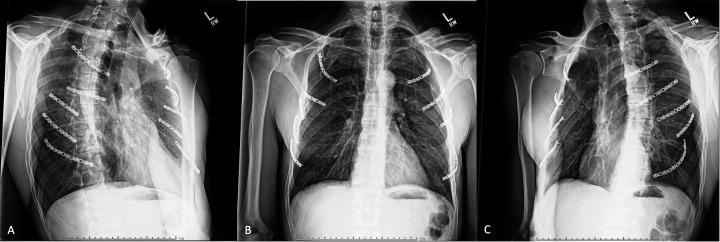

Abstract Image

Methods: This is a retrospective review of 125 patients who underwent open reduction internal fixation of flail segmental rib fractures at our urban Level 1 trauma center. Initial plain films and CT were compared with follow-up plain film imaging at 3 months to assess radiographic outcomes, fracture healing, fixation failure, or residual deformity. Clinical outcomes such as length of intensive care unit (ICU) stay, length of ventilatory support, associated pneumonia, duration until chest tube removal, and need for additional rib surgery were analyzed.

Results: Fixation of a single end of segmental rib fractures and flail segments was associated with decreased incidence of fracture union at 3 months postoperatively (43/55 vs 65/70, respectively; p=0.018) but failed to show any difference in fracture collapse (50/55 vs 67/70, respectively; p=0.223). There were no differences between postoperative ICU length of stay (4.18±5.54 vs 4.62±4.48 days, respectively; p=0.690), postoperative ventilatory status (29/55 vs 38/70, respectively; p=0.840), duration of ventilatory support (3.52±4.69 vs 4.34±5.87, respectively; p=0.430), or associated pneumonia (7/55 vs 8/70, respectively; p=0.770).

Conclusions: These data support that fixation of both sides of flail segment rib fractures results in improved rib fracture union at 3 months postoperatively. However, fixation of both sides of flail segments does not appear to result in any difference in fracture collapse or clinical perioperative outcomes.